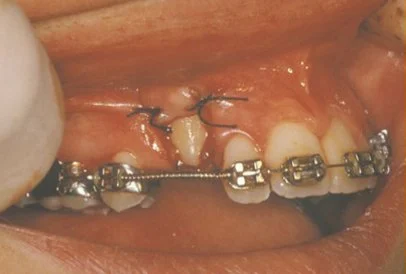

In a simple surgical procedure performed in the surgeon’s office, the gum on top of the impacted tooth will be lifted up to expose the hidden tooth underneath. If there is a baby tooth present, it will be removed at the same time. Once the tooth is exposed, the oral surgeon will bond an orthodontic bracket to the exposed tooth. The bracket will have a miniature gold chain attached to it. The oral surgeon will guide the chain back to the orthodontic arch wire where it will be temporarily attached. Sometimes the surgeon will leave the exposed impacted tooth completely uncovered by suturing the gum up high above the tooth or making a window in the gum covering the tooth (on selected cases located on the roof of the mouth). Most of the time, the gum will be returned to its original location and sutured back with only the chain remaining visible as it exits a small hole in the gum.

Shortly after surgery (same day-14 days) the patient will return to the orthodontist. A rubber band will be attached to the chain to put a light eruptive pulling force on the impacted tooth. This will begin the process of moving the tooth into its proper place in the dental arch. This is a carefully controlled, slow process that may take up to a full year to complete. Remember, the goal is to erupt the impacted tooth and not to extract it! Once the tooth is moved into the arch in its final position, the gum around it will be evaluated to make sure it is sufficiently strong and healthy to last for a lifetime of chewing and tooth brushing. In some circumstances, especially those where the tooth had to be moved a long distance, there may be some minor “gum surgery” required to add bulk to the gum tissue over the relocated tooth so it remains healthy during normal function. Your dentist or orthodontist will explain this situation to you if it applies to your specific situation.